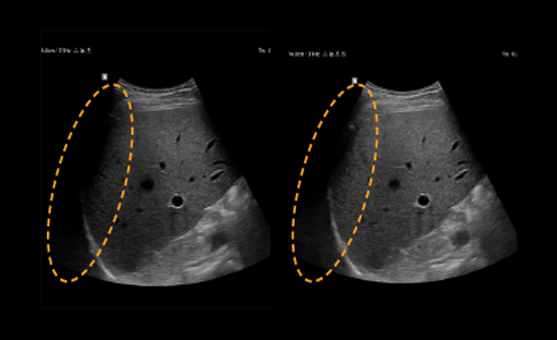

Obțineți informații detaliate bazate pe performanța remarcabilă a imaginii, alimentată de motorul principal de imagine al Samsung, Crystal Architecture. Motorul de imagistică premium combină beneficiile procesării avansate a imaginilor 2D și expresia detaliată a procesării semnalului de culoare.

Filtrul de reducere a zgomotului îmbunătățește definiția marginilor și creează imagini 2D clare pentru performanțe optime de diagnosticare. În plus, ClearVision oferă optimizare specifică aplicației și rezoluție temporală avansată în modul de scanare în timp real.